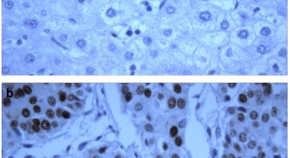

Mitochondrial interaction of HKDC1 is essential for its pro-proliferative role in LC. When HKDC1 is ablated in liver cancer cells, mitochondrial dysfunction occurs which results in decrease ATP in the cells. The cancer cells react to decreased cellular energy by increasing glucose uptake. Also due to mitochondrial dysfunction there is enhanced ER stress and ER-mitochondrial interaction, leading to more calcium flux into the mitochondria. This multi-pronged effects of HKDC1 ablation leads to decreased cellular proliferation in LC.